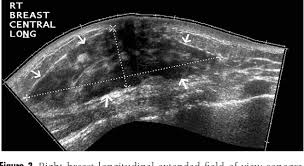

Women with inflammatory breast cancer often have dense breasts, which can make it difficult to see signs of cancer on a mammogram. Instead of forming a lump, the disease causes the affected breast to become swollen, red and tender, often in a matter of days or weeks. Inflammatory breast cancer (ibc) is a rare, aggressive form of breast cancer. Did not respond to antibiotic and was referred for biopsy. Inflammatory breast cancer is generally treated first with systemic chemotherapy to help shrink the tumor, then with surgery to remove the tumor, followed by radiation therapy.this approach to treatment is called a multimodal approach. However, you should be careful to notice it because people often get confused with a breast infection with this disease. Top 2 pictures are prior the first chemo. These cells block the lymph vessels. This is an inflammatory breast cancer organization with a lot of great information, including pictures! An early sign of inflammatory breast cancer is discoloration of the breast. It blocks the lymph vessels in the skin of your breast. What is inflammatory breast cancer? Inflammatory breast cancer (ibc) is a rare type of breast cancer often starts in the soft tissues of the breast and causes the lymph vessels in the skin of the breast to become blocked.

Inflammatory breast cancer (ibc) is a rare and aggressive form of breast cancer that often appears as a rash or an irritated area of skin. Photos of ibc symptoms these photographs show typical visual symptoms that appear at time of diagnosis, before treatment. These vessels are part of the lymphatic system.they drain fluid from tissues, collecting and filtering out bacteria and any waste materials from the body's cells. Did not respond to antibiotic and was referred for biopsy. Most cases are invasive ductal carcinomas, which develop in the cells lining the milk ducts and spread throughout the breast. Although it is often a type of invasive ductal carcinoma, it differs from other types of breast cancer in its symptoms, outlook, and treatment. I have inflammatory breast cancer which was firstly diagnosed as mastitis in jan 09. Your physician is your best guide.